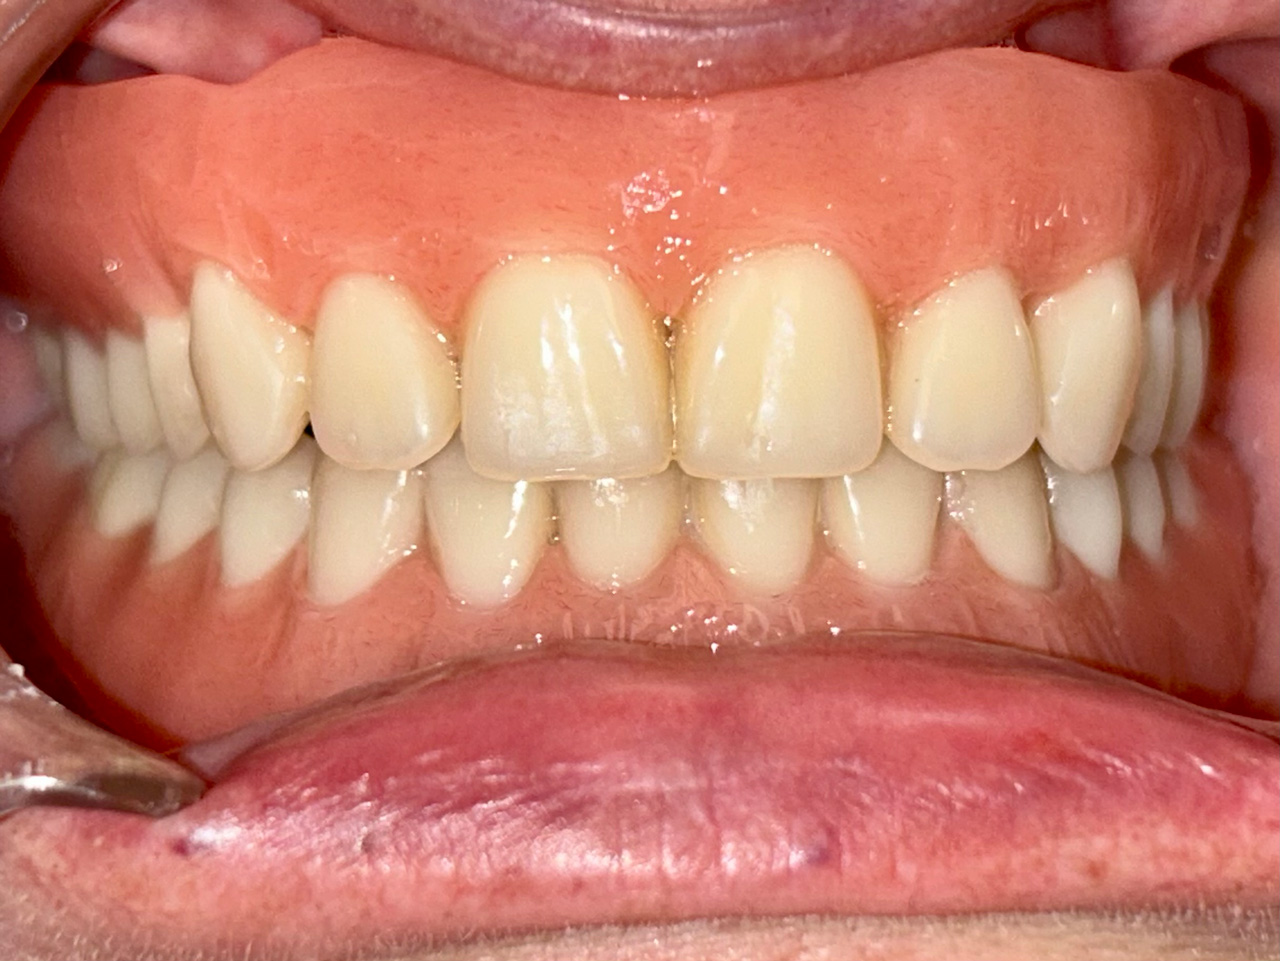

Teljes szájüregi rehabilitáció két lépésben

Ismét egy teljes szájüregi rehabilitáció két lépésben. Először az alsó fogak lettek kihúzva és azonnal implantálva, híddal ellátva, majd később a felső. IHDE svájci azonnal terhelhető implantátumok és cirkónium hidak. Dr. Kelemen Péter és a Symbion Fogtechnika közös munkája.